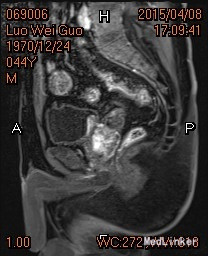

盆腔MRI弥散成像 平扫+增强:1.膀胱三角区类梭形异常信号影,未除外膀胱壁肿瘤累及尿道前列腺部可能,建议膀胱镜检查协诊。 2.前列腺增大。 双肾输尿管膀胱(前列腺)(超声诊断报告书):膀胱肿物,未排Ca。前列腺肥大伴钙化。双肾、双输尿管超声检查未见异常。